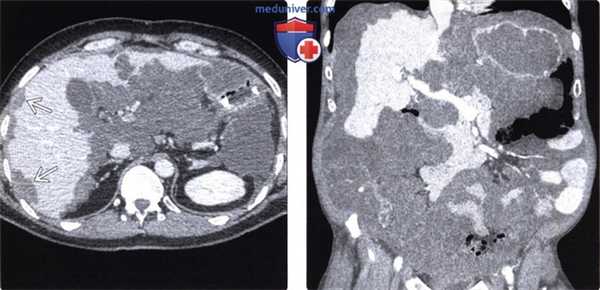

(Слева) На аксиальной КТ с контрастным усилением визуализируется печень, имеющая характерный «фестончатый» вид за счет наличия по периферии неболь -ших вторичных очагов. Эти очаги имеют низкую плотность (около +20 ед. Хаунсфилда), немного превышающую плотность «простой» жидкости.

(Справа) На корональной КТ с контрастным усилением у этого же пациента визуализируются множественные вторичные очаги низкой плотности, занимающие большую часть объема брюшной полости. Не удивительно, что у пациента часто возникают симптомы кишечной обструкции.